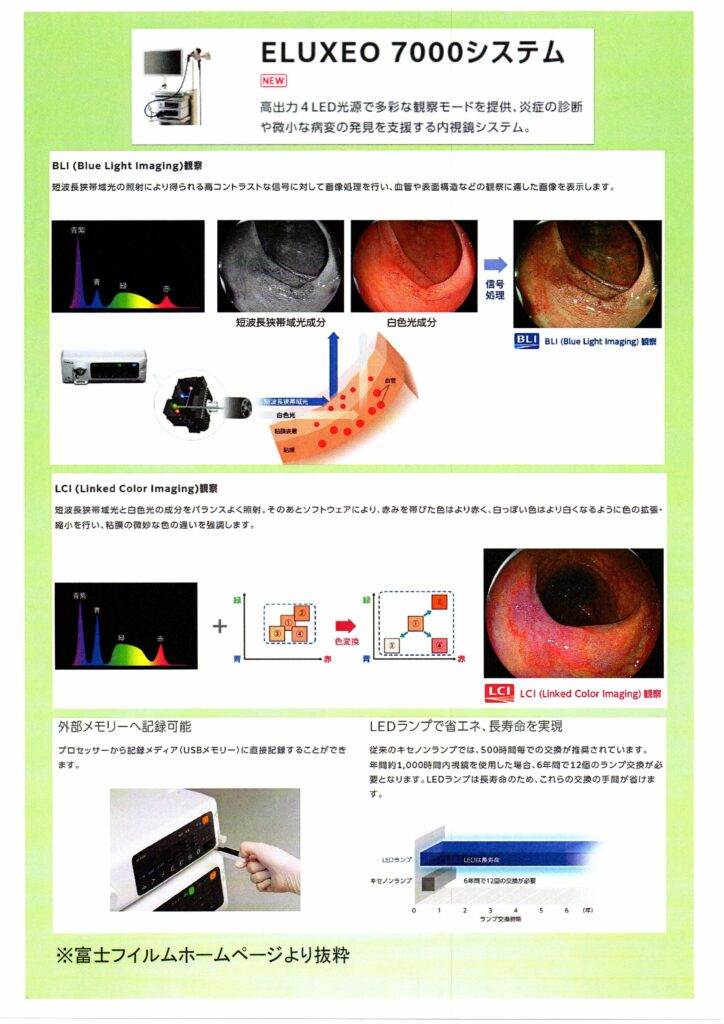

2020年10月1日より内視鏡センターに名古屋市内初導入の内視鏡システムが導入されました。

・富士フイルム ELUXEO7000 1台

狭帯域光観察:NBI(Narrow Band Imaging)BLI(Blue LASER Imaging)

このシステムでは、狭帯域化された2つの波長の光を用いることにより、発見が困難な病変を見つけたり、がんの範囲の詳細な診断をすることが可能です。 特に、食道がんや咽頭、喉頭のがんはNBIで観察することで、発見の精度が上がります。